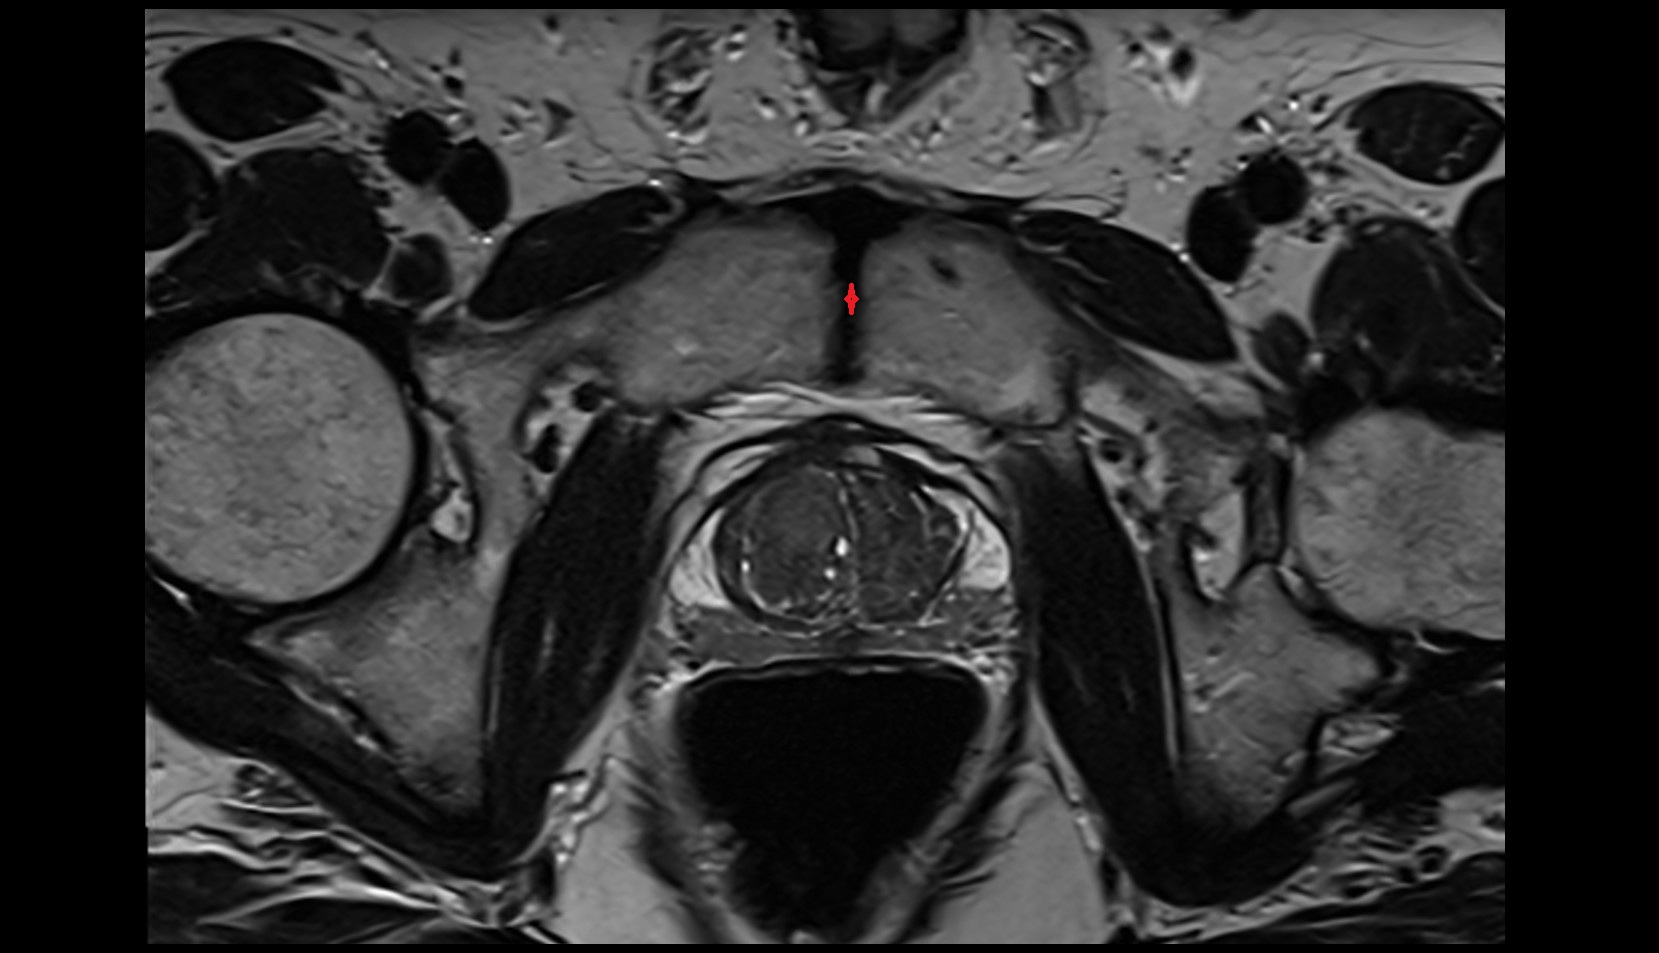

- Peripheral zone of prostate

- Anterior Fibromuscular Stroma of prostate

- Central zone of prostate

- Transitional zone of prostate